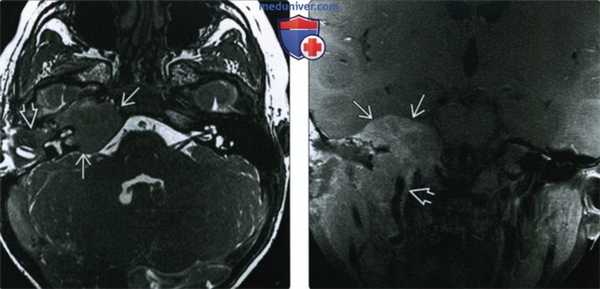

(Слева) При аксиальной МРТ Т2 FSE определяется распространенная опухоль с гипоинтенсивным сигналом - типичное новообразование с высокой целлюлярностью. Опухоль поражает полость среднего уха и вершину пирамиды. При повторной биопсии через три года подтвердилась РМС.

(Справа) При корональной МРТ Т1 ВИ С+ FS определяется интракраниальное распространение, типичное для пациентов с параменингеальной РМС. Также обратите внимание на распроаранение РМС вдоль вертикального сегмента каменистой части внутренней сонной артерии.